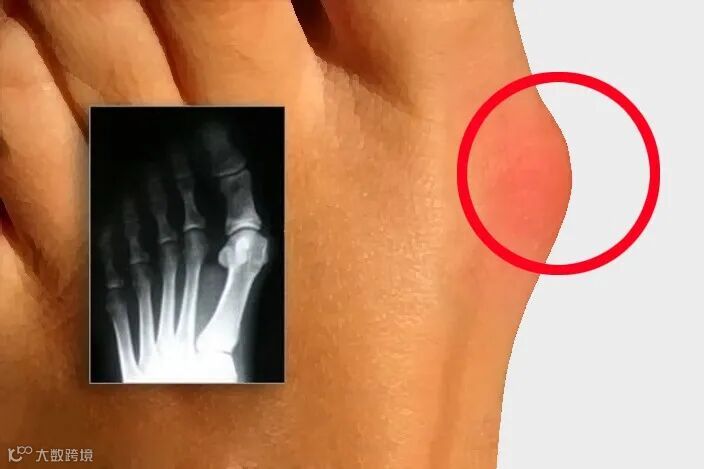

拇外翻的症状?

拇趾外偏:拇趾向外倾斜,甚至重叠到第二趾上。

拇趾关节突出:内侧关节处形成一个明显的骨性突起。

疼痛与不适:尤其是在穿鞋时,突起部位容易摩擦,导致疼痛和炎症。

皮肤问题:突起部位的皮肤可能会红肿、发炎,甚至形成老茧或水泡。

手术治疗:严重情况下,建议手术治疗,因为拇外翻通常持续进展。

中心医院拇外翻采取微创小切口矫形手术,术后当天即可行走,不影响生活工作。